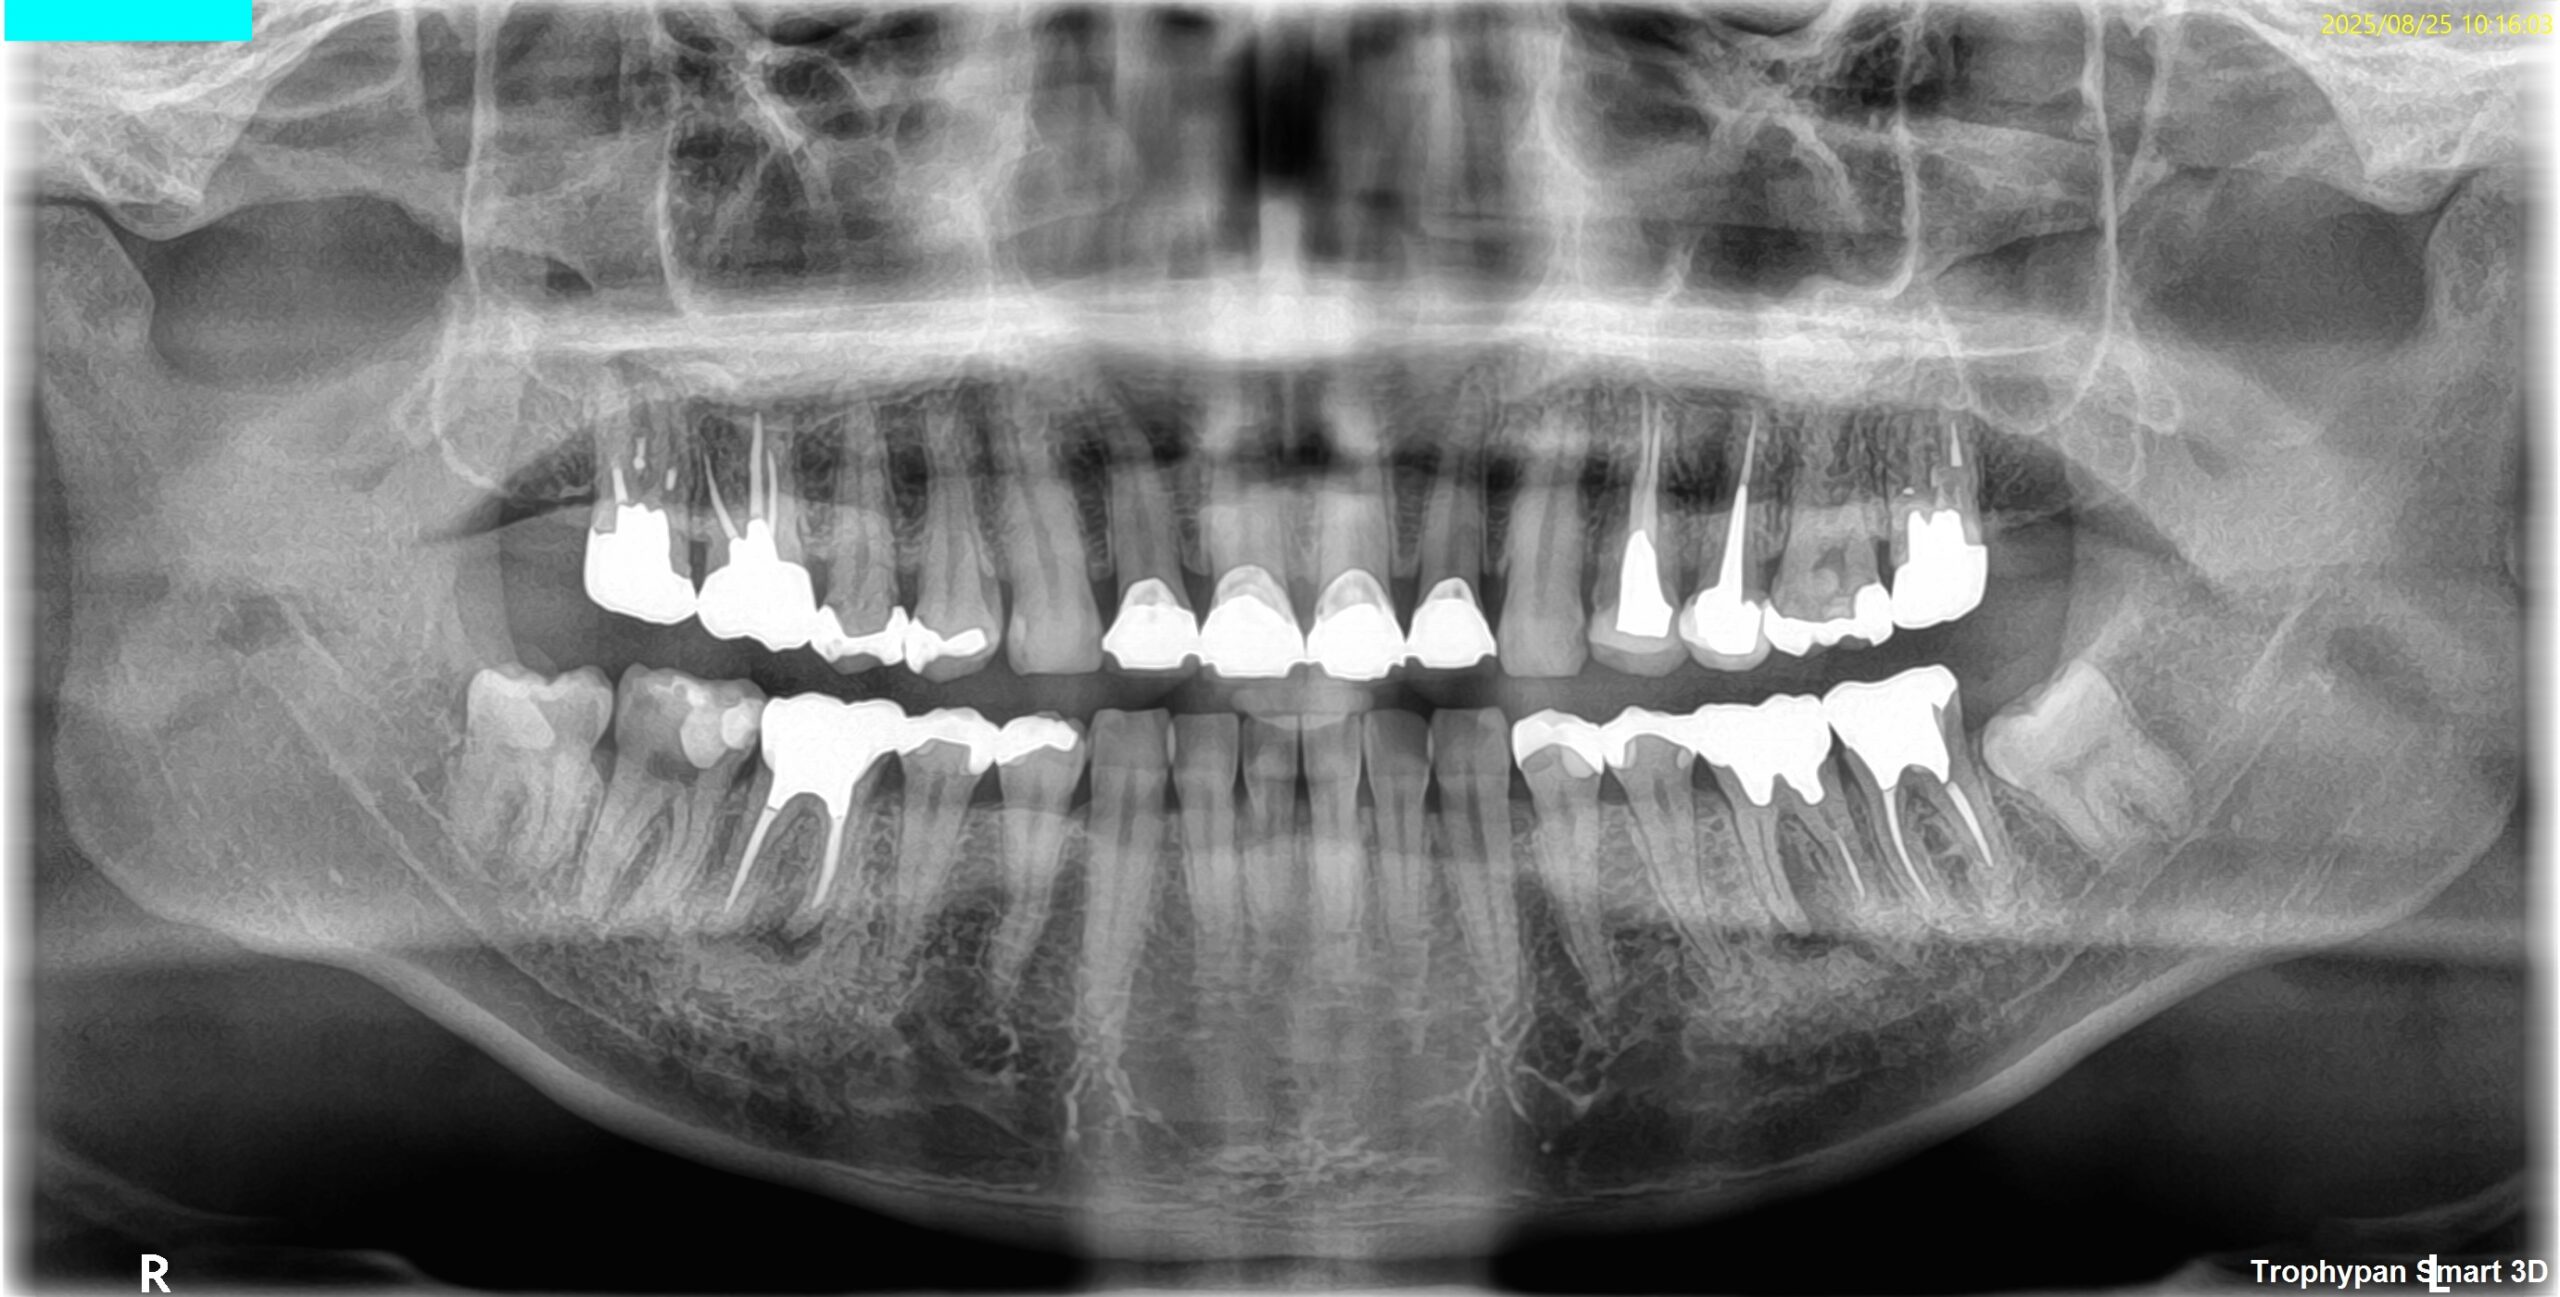

OPG(2025.8.25)